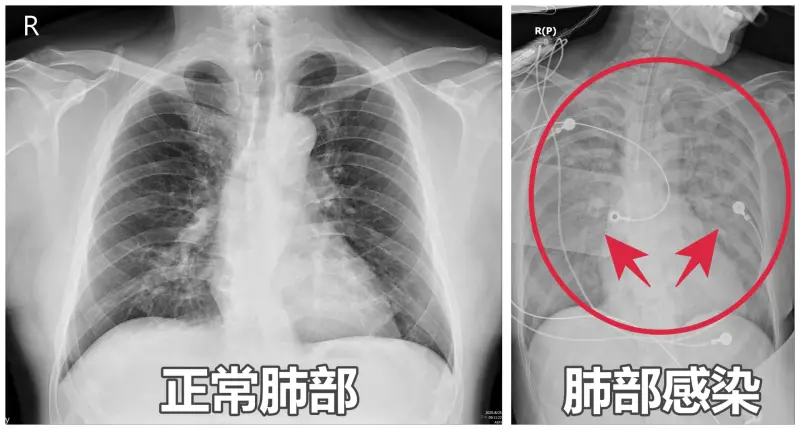

亞洲大學附屬醫院醫師謝逸安表示,65歲李姓闆娘最近嚴重嗜睡、咳嗽、胃口差,被家人形容「像靈魂出竅」,日前因全身無力送急診,檢查發現血氧僅剩90%,且X光竟顯示「雙肺一片白」,確診為肺炎,立即送進加護病房,治療整整1週才出院。

▲謝逸安醫師提醒,接種RSV疫苗、肺炎鏈球菌疫苗及流感疫苗,都是降低重症、死亡風險的有效方法。(圖/亞大醫院提供) 謝逸安指出,肺炎不等於新冠肺炎,流感、呼吸道融合病毒(RSV)、肺炎鏈球菌等,都是常見的社區型肺炎元兇,高風險族群包含60歲以上長者、孕婦、幼童及免疫力較低的慢性病患,一旦感染,常迅速出現「大白肺」,甚至併發敗血症。